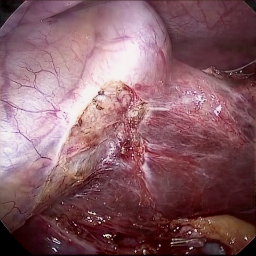

Refer to caption (a) Input Refer to caption (b) case1 Refer to caption (c) case2 Refer to caption (d) case3 Refer to caption (e) Ours Refer to caption (f) Target

Figure 4: Ablation comparisons sampled from the DesmokeData and LSD3K datasets. The first two rows are from DesmokeData and the last two rows are from LSD3K. (settings: case1 = ADA+CrossGating, case2 = DHA+CrossGating, case3 = DHA+ADA).

IV-D Ablation Studies

To validate the effectiveness and individual contributions of the core components of our proposed RGA-Net, we conducted a series of ablation experiments on the DesmokeData dataset. We systematically analyzed the impact of our key designs: the DHA module, the ADA module, and the Cross-Gating (CG) mechanism for feature fusion. In these studies, we created several variants of our network by removing or replacing one component at a time and evaluated their performance. The quantitative results of these experiments are presented in Table II, and qualitative visual comparisons are shown in Fig. 4.

IV-D1 Effectiveness of the Dual-Stream Hybrid Attention Module

The DHA module is designed to capture both local surgical details and global illumination changes by combining shifted window attention with a frequency-domain processing branch. To ablate its effect, we replaced the DHA modules in the encoder with standard Swin Transformer blocks, thus removing the spectral pathway and the hybrid attention mechanism. As demonstrated in Table II, this variant experienced a significant drop in performance. This decline highlights the importance of integrating frequency-domain information, which is crucial for handling the complex light scattering caused by surgical smoke and restoring high-frequency textural details. The results confirm that the dual-stream approach provides a richer feature representation than spatial attention alone.

IV-D2 Effectiveness of the Axis-Decomposed Attention Module

We then investigated the contribution of the ADA module, which is employed in the decoder and latent space to efficiently process multi-scale features. We created a variant where the ADA modules were substituted with a more conventional self-attention mechanism without the block and grid axis decomposition. The results in Table II show a clear degradation in performance for this variant compared to the full model. This outcome validates that factorizing attention along two distinct axes allows the model to capture both fine-grained local patterns and long-range spatial dependencies more effectively and efficiently. The ADA module’s design provides a powerful yet computationally manageable way to model complex feature relationships during the reconstruction phase.

IV-D3 Effectiveness of the Cross-Gating Mechanism

Finally, we analyzed the efficacy of the cross-gating mechanism used for multi-scale feature fusion between the encoder and decoder. We replaced our CG blocks with a standard skip-connection method, specifically simple concatenation followed by a convolutional layer, as is common in many U-Net-based architectures. As shown in Table II, this change resulted in a substantial performance decrease. This finding underscores the superiority of the bidirectional feature modulation offered by our CG mechanism. Unlike simple fusion, cross-gating allows the encoder and decoder pathways to selectively amplify relevant features and suppress irrelevant information from each other, leading to a more refined and effective integration of multi-scale context, which is vital for high-quality image reconstruction.

In conclusion, the ablation studies comprehensively demonstrate that each of our proposed components—DHA, ADA, and CG—is integral to the overall performance of RGA-Net. The full model consistently outperforms all ablated variants, proving the synergistic benefits of our architectural design for the challenging task of surgical smoke removal.